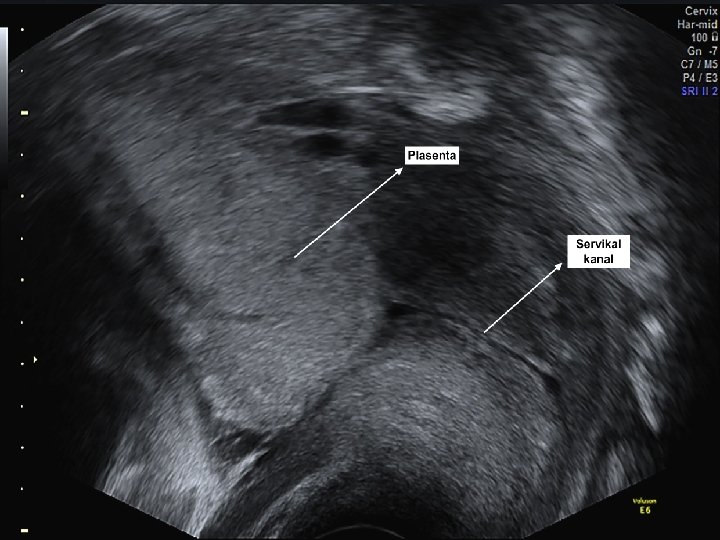

Plasental Faktörler-IUGR • Azalmış plasental perfüzyona yol açan anormal plasentasyon fetal gelişme geriliği ile en çok ilişkilendirilmiş patolojidir. • Fetal gelişim kısıtlılığı ile bazı plasental bozukluklar (dekolman, enfarkt, sirkumvallat plasenta, hemanjiom ve korioanjiom) ve umblikal kord anormallikleri (velamantöz veya marjinal kord insersiyonu) de ilişkilendirilmiştir.

• Plasentadaki anormal vasküler bağlantılar çoğul gebeliklerle ilgili ciddi gelişme geriliği ve uyumsuz büyümeden sorumlu tutulmuşlardır. • Plasenta akreata ve plasenta previa gibi diğer plasental bozukluklar ile fetal gelişme geriliği arasında tutarlı bir ilişki gösterilememiştir. • Bütün gebeliklerin yaklaşık %1’inde tek umblikal arter bulunur. • Eşlik eden anatomik veya kromozomal anormalliklerin yokluğunda tek umblikal arter saptanması bazı çalışmalarda fetal büyüme geriliği ile ilişkilendirilmiş iken bazı çalışmalarda bu ilişki gösterilememiştir.

• İNTRAUTERİN GELİŞME GERİLİĞİNİN EN SIK NEDENİ PLASENTAL YETMEZLİKTİR. !! • IUGR’YE YOL AÇAN PLASENTAL ANOMALİ PLASENTA CIRCUMVALLATA !!